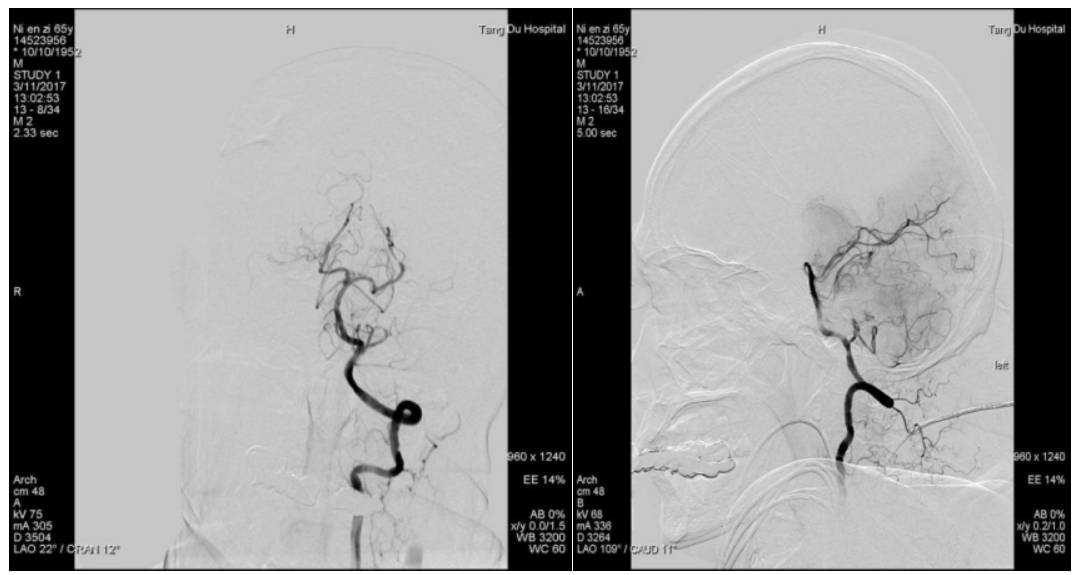

术前脑血管造影显示左侧大脑中动脉急性闭塞,代偿不佳

微导管通过血栓后造影显示远端血管通畅